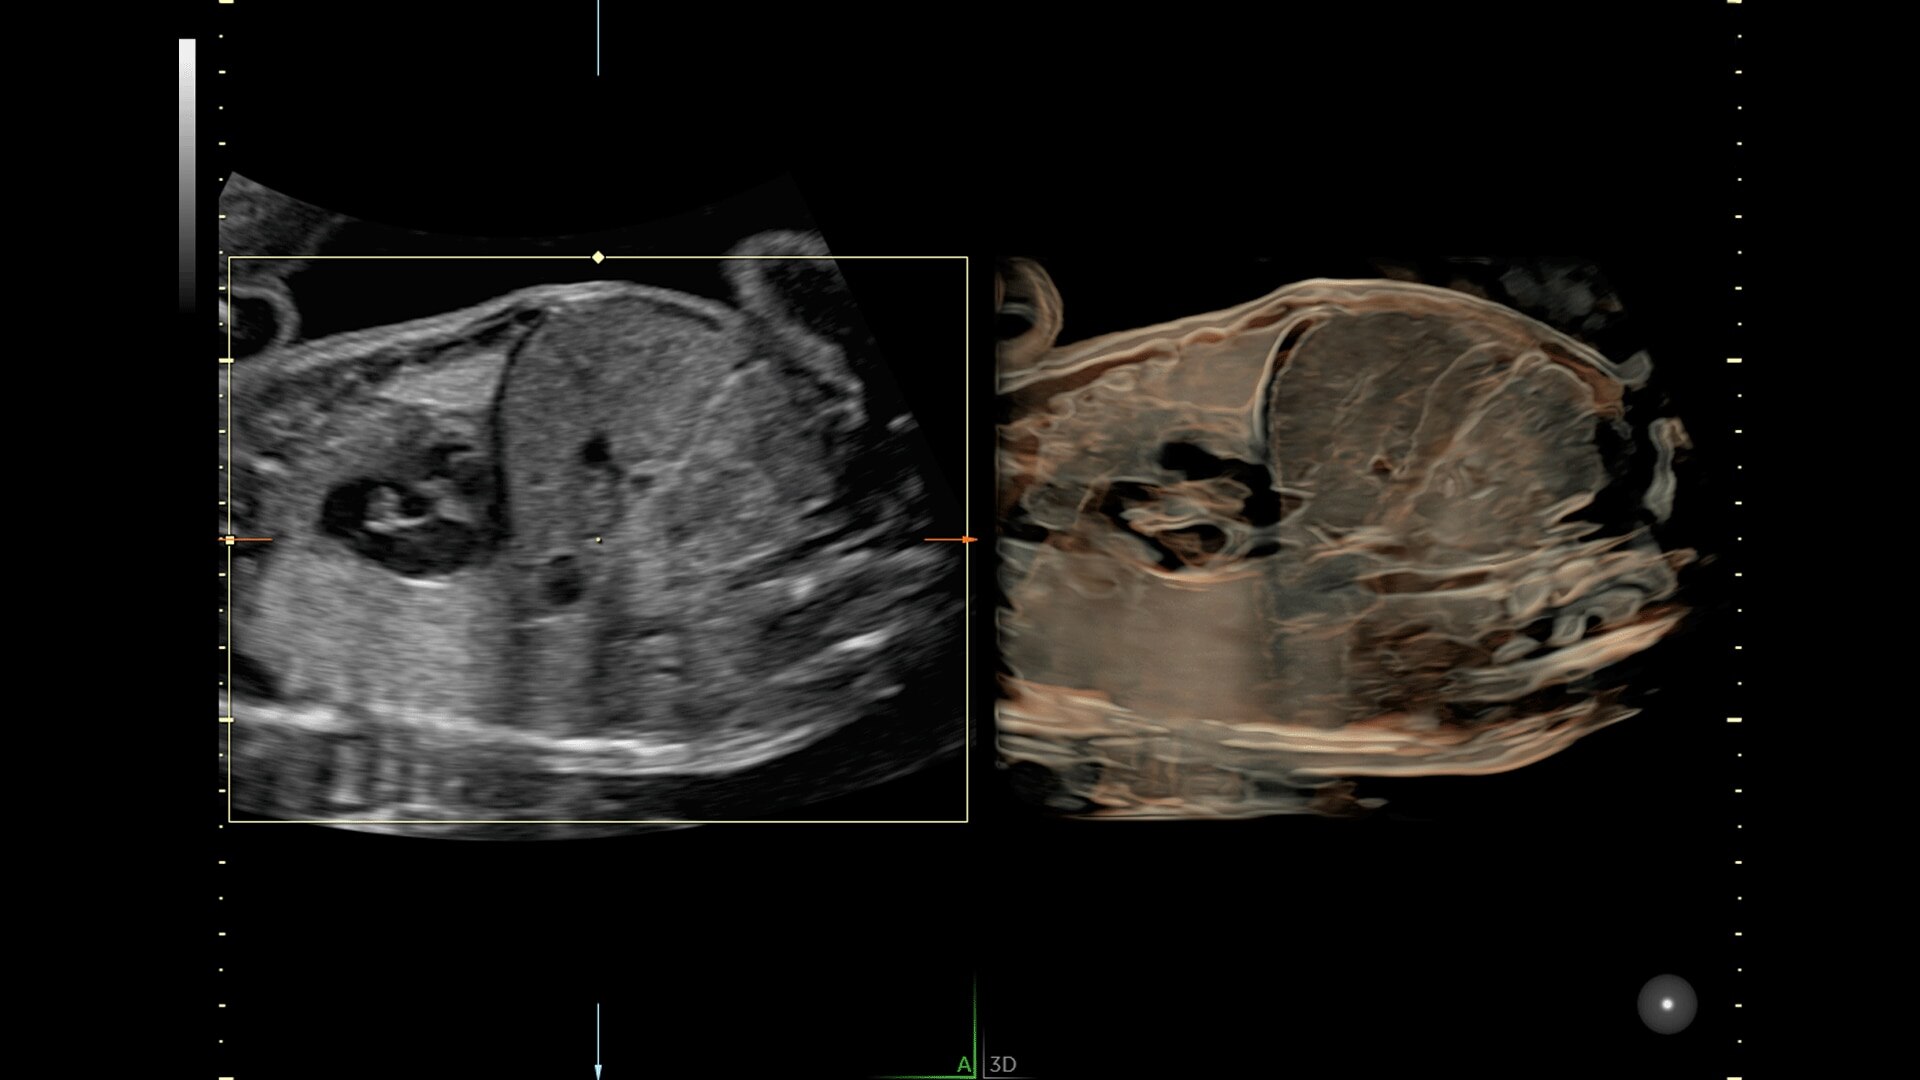

Generate spectacular 2D/3D and color Doppler images with increased penetration and stunning clarity, to help visualize critical details needed for diagnostic assurance. The Lyric Architecture unlocks new imaging and processing power to expand your imaging capabilities for years to come